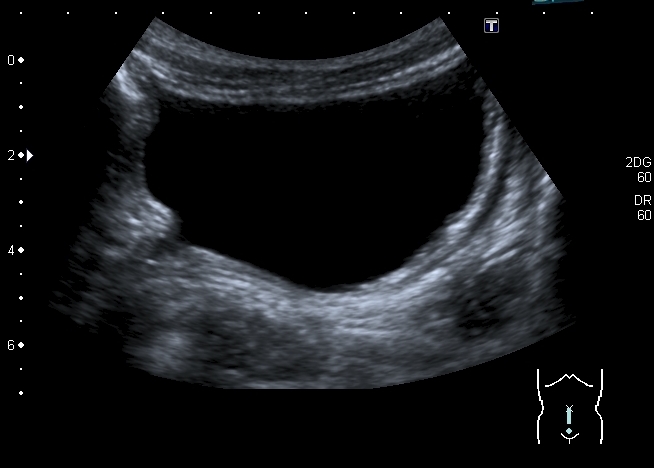

Мочевой пузырь:

"Маленькие белые почки" с расширением ЧЛС и мочеточников, умеренной латерализацией устьев, без видимых на высокочастотном УЗИ кист. Печень без видимых на высокочастотном УЗИ кист. Опухоль слева.

Посмотрел шейку пузыря - уретральной "воронки" не видел.